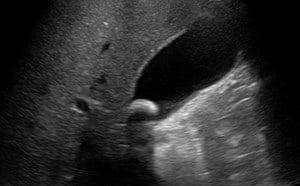

- Depending on their location, you may also identify kidney stones:

- Stones within the kidney - look for bright objects that cast a shadow within the kidney.

- Figures 5 and 6. Renal stones (arrows) with shadowing

- Stones at the ureteropelvic junction - look for a bright object that casts a shadow at the hilum as the renal pelvis narrows to form the ureter.